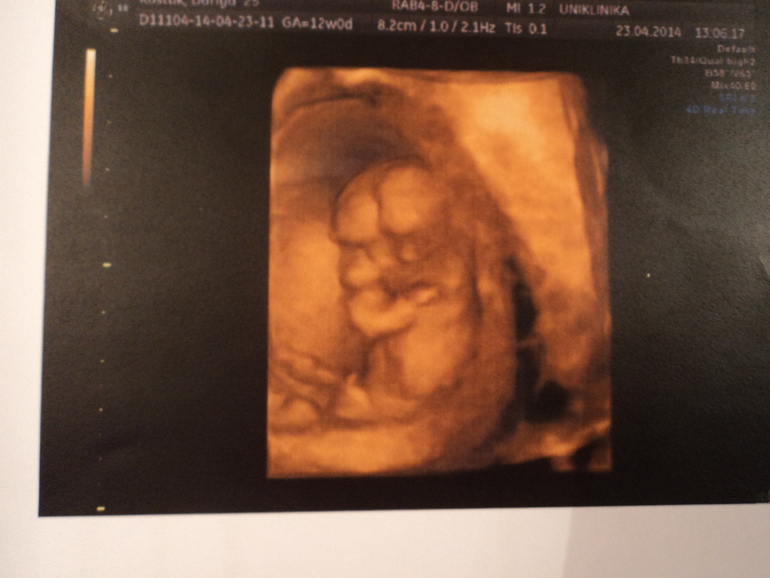

Первый скрининг! )))

Это UNIклиника на Оболонской набережной, 11! Мне там очень понравилось, меня врач туда именно направляла. Аппаратура у них бомба! )

Ух ты! Прелесть baby.gif и такое УЗИ качественное!

Спасибо! ))) Ага, типа 3Д! )

Я просто помню свое на 12 неделе) толком ничего не видно.

мне кажется, у Вас будет мальчик)

я тоже так сразу подумала, но нет, врач сказала и показала — это кишка! )))